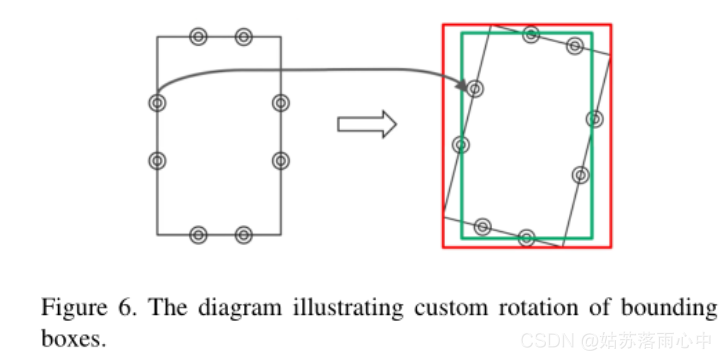

图像数据预处理与图像增强

原始图像按比例缩放为512×512像素分辨率,由于原始的挑战数据集不是很大,因此采用了以下图像增强来减少过拟合:轻微旋转(最多6度);移位,缩放,剪切;水平翻转;对于某些图像,模糊处理,添加噪声,进行伽玛值随机变化;有限提高亮度/伽玛增强量等。